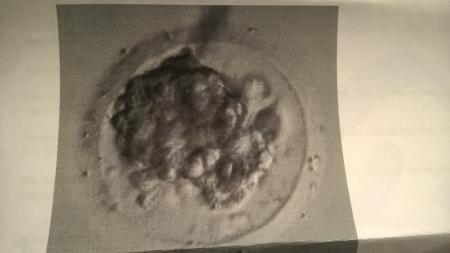

da bin ich ja sehr Froh das es Normal ist denn hatte gestern schon zeihen und so ein mens artiges Gefühl und mein rechtes bein tat mir weh einfach komisch aber ich denke nicht das davon war nur die Aufregung naja. ich war heute schon wider arbeiten dann denke ich nicht die ganze zeit drüber nach ich hatte jetzt schon so viel Geduld dann kann ich auch noch 13 tage warten ^^ ich wollte euch ein Bild von meiner Blasto da lassen und fragen wie findet ihr sie liebe gruß lara

Bild zu